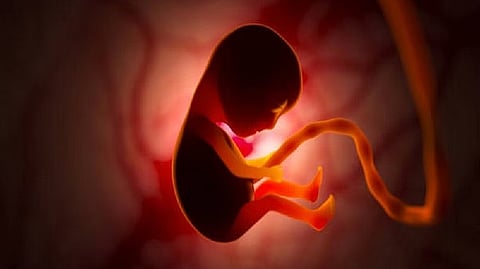

WASHINGTON: Published in the journal ‘Proceedings of the National Academy of Sciences’ (PNAS), a new study found links between social disadvantages and foetal brain development.

Researchers examined 289 healthy newborns from socially diverse families in the United States using diffusion MRI scans shortly after birth. The analysis revealed that prenatal exposure to measures of social disadvantage was associated with altered microstructure of white matter in frontolimbic pathways of the brain that are important for socioemotional development.